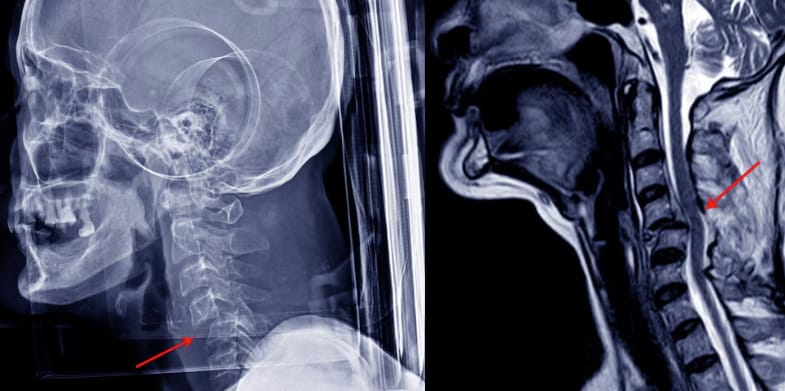

Pesquisadores da UFRJ desenvolveram um medicamento 100% nacional

que permitiu que quatro pacientes paraplégicos voltassem a apresentar movimentos.

Lesão medular sempre foi tratada como sentença definitiva.

Agora, essa ideia começa a ruir.

Lesões medulares estão entre os maiores desafios da Medicina moderna:

dano neurológico complexo

regeneração limitada

pouca resposta a terapias tradicionais

O que esse estudo mostra é simples e poderoso:

o sistema nervoso pode responder quando a ciência é bem feita.

É sobre reabrir caminhos neurológicos que a Medicina havia desistido de explorar.